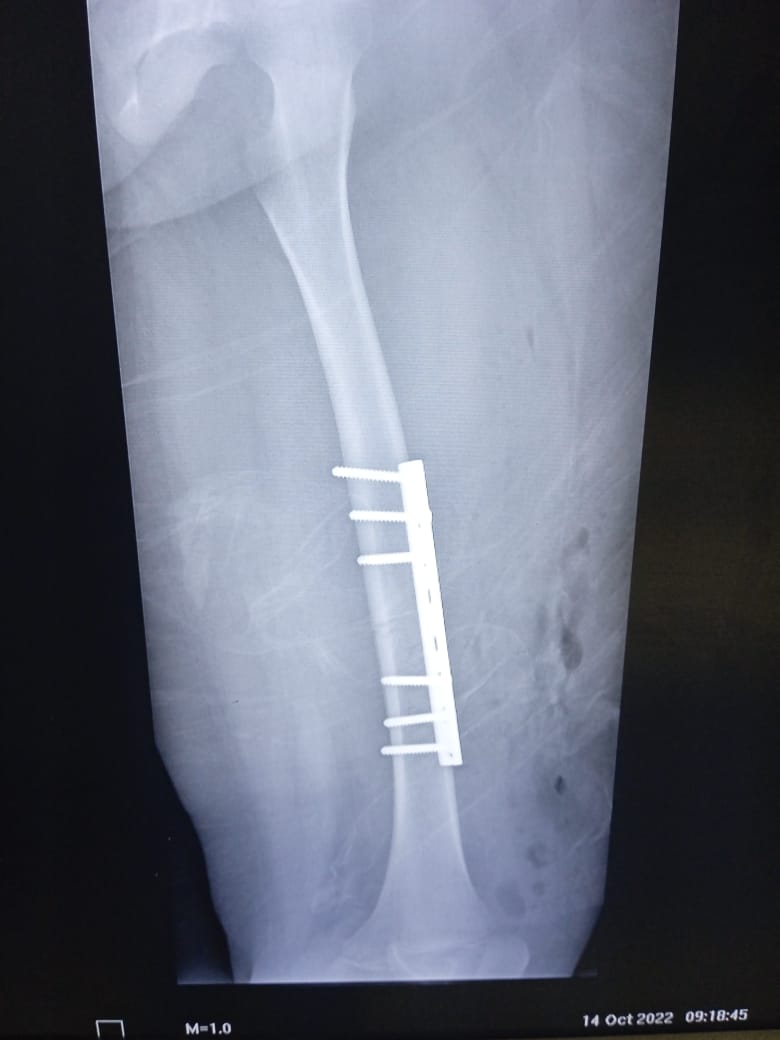

| Fue necesaria la colocación de placa y seis tornillos en la pierna izquierda |

El Hospital General de Zona (HGZ) No. 35 en Cosamaloapan del Instituto Mexicano del Seguro Social (IMSS) en Veracruz Sur realizó una cirugía exitosa a Arianna, niña de 8 años, tras sufrir un aparatoso accidente en motocicleta, que ocasionó una fractura de fémur izquierdo. El subdirector médico del HGZ No. 35, doctor Miguel Parra Espinoza, explicó que al arribar la niña al área de Urgencias fue estabilizada y recibió el tratamiento inicial, para posteriormente pasar al área de Traumatología donde le realizaron los estudios y solicitud de material para ser intervenida lo más pronto posible. "El pronóstico para Arianna es bueno, la cirugía no tuvo ningún inconveniente, actualmente la niña ya está por iniciar la rehabilitación que le permitirá, al paso del tiempo, reanudar sus actividades diarias", explicó el subdirector médico. El HGZ No. 35 cuenta con un área de Rehabilitación Física donde Arianna tendrá su proceso a terapias y ejercicios que le permitirá recobrar la movilidad de su pierna, bajo el cuidado de especialistas en la materia. La mamá de Arianna, Viridiana explicó que desde el arribo de la niña al HGZ No. 35 IMSS recibió atención inmediata hasta completar el protocolo de estudios para la cirugía, donde le colocaron una placa de seis tornillos. "Me indicó el médico que mi hija necesitaba una cirugía, la fractura era delicada; nos explicaron el proceso que debía llevar mi hija. Agradecemos al doctor Camacho que haya realizado la operación, porque él, a pesar de que es directivo, realizó la cirugía a mi hija", dijo. A nombre de su esposo, hija y de ella misma, agradeció a todo el personal IMSS que hace lo posible para que Arianna retome sus actividades diarias.